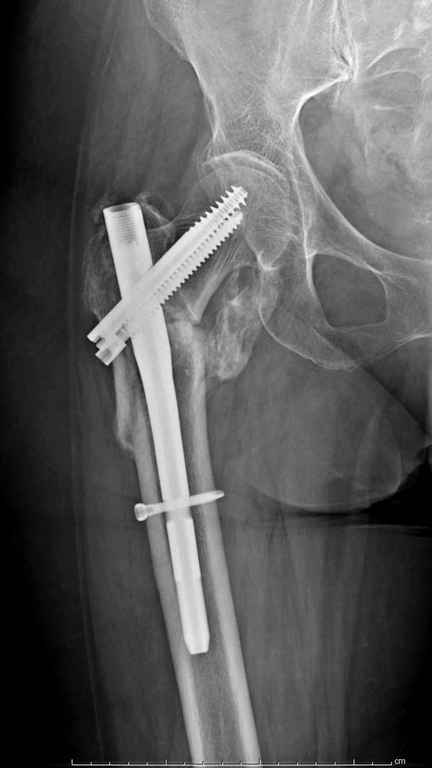

Предугадать распространение линий перелома при чрезвертельных и оскольчатых переломах трудно, поэтому для принятия правильного решения рекомендуется Компьютерно Томографические исследование.

При отсутствии КТ, снимок на вытяжении поможет увидеть общую картину расположения отломков, особенно потенциальные места введения импланта. Риск раскола в этом случае огромный, поэтому больной должен быть дообследован.

А так для лечения оскольчатых переломов подходят все методы, включая интра- и экстрамедуллярные в зависимости от опыта и наличия импланта.

Здесь пара похожих случаев.